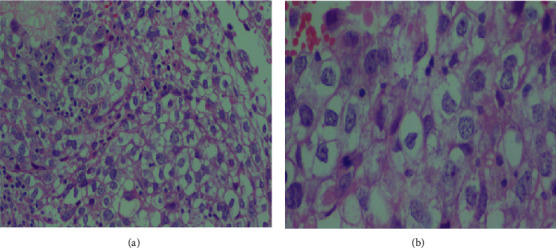

简介原发性对角线外生殖细胞瘤(EGCTs)是一种非常罕见的临床疾病,最常见于男性。在女性中,胎盘、骨盆、子宫、大脑和纵隔是最常见的生殖细胞瘤部位,其组织学主要表现为非生殖细胞瘤。在本报告中,我们介绍了一例年轻女性患者的原发性宫颈胚胎发育不良瘤。病例报告。一名 18 岁的无生育能力女性因 12 个月的阴道出血和分泌物病史前来就诊。血常规检查和血清肿瘤标志物水平均在正常范围内。胸部 X 光检查正常。高分辨率盆腔磁共振成像显示,宫颈阴道肿块轮廓清晰,大小为 8 × 6 × 5 厘米,向阴道口扩展,呈轻度均质对比增强。患者在麻醉状态下经阴道进行了切口活检,组织学检查结果与畸形精原细胞瘤一致。再次复查盆腔磁共振成像显示,肿块缩小了 70% 以上。患者接受了 4 个周期的博来霉素、依托泊苷和顺铂化疗。在获得部分反应后,又进行了盆腔外放射治疗。放疗 3 个月后,对比腹盆腔 CT 扫描显示宫颈阴道肿块复发,并向盆腔侧壁扩展。患者因生殖细胞瘤复发开始接受伊佛酰胺、紫杉醇和顺铂(ITP)二线化疗,但后来死于肾积水、慢性贫血和败血症:结论:子宫颈是原发性生精细胞畸形瘤的一个非常不寻常的部位,其临床病程可能非常凶险。要确诊该病,尤其是对宫颈病变的年轻患者,必须高度怀疑并进行全面检查。

Introduction: Primary extragonadal germ cell tumors (EGCTs) are a very rare clinical encounter most commonly reported in males. Among females, the placenta, pelvis, uterus, brain, and mediastinum are the most common extragonadal sites and predominantly display nondysgerminoma histology. In this report, we present a case of a primary cervical dysgerminoma in a young female patient. Case Report. An 18-year-old nulligravid woman presented with a 12-month history of vaginal bleeding and discharge. Routine blood tests and serum levels of tumor markers were within normal limits. The chest X-ray was normal. A high-resolution pelvic MRI showed a well-defined lobulated cervicovaginal mass measuring 8 × 6 × 5 cm expanding into the vaginal canal with mild homogenous contrast enhancement. An incisional biopsy was performed vaginally under anesthesia, and histologic findings were consistent with dysgerminoma. A repeat follow-up pelvic MRI was done and showed a reduction in the size of the mass by more than 70%. The patient was treated with 4 cycles of bleomycin, etoposide, and cisplatin chemotherapy. Additional external pelvic beam radiation treatment was administered for a partial response. After 3 months of radiotherapy, a contrast abdominopelvic CT scan showed a recurrent cervicovaginal mass with extension to the pelvic sidewalls. The patient was initiated with ifosfamide, paclitaxel, and cisplatin (ITP) as second-line chemotherapy for a recurrent germ cell tumor but later died from hydronephrosis, chronic anemia, and sepsis.